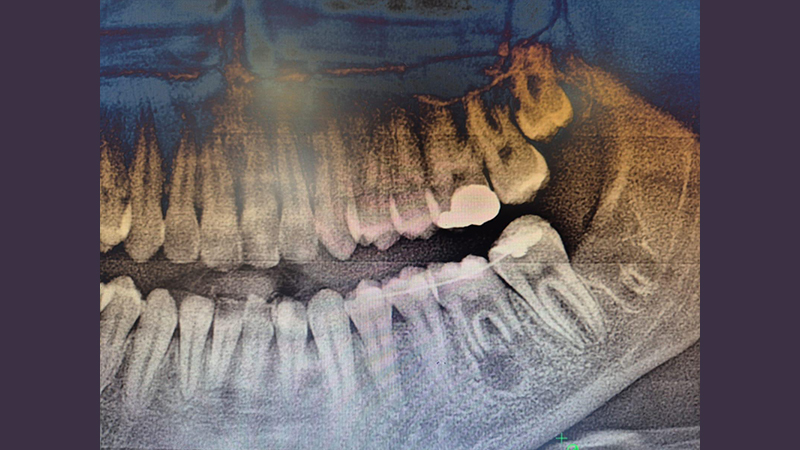

Karabük Ağız ve Diş Sağlığı Eğitim ve Araştırma Hastanesi’ne gelen 16 yaşındaki hastanın ileri düzey çürük nedeniyle tedavi amaçlı olarak bir daimi azı dişi çekildi. Çocuk yaşta çene gelişimi devam ettiği için implant uygulaması gibi yöntemlerin uygun görülmediği hastaya kendi ağzında kemik içinde gömülü halde bulunan üçüncü azı dişi (yirmi yaş dişi), Endodonti Anabilim Dalı öğretim üyesi Doç. Dr. Olcay Özdemir ile Ağız, Diş ve Çene Cerrahisi Anabilim Dalı öğretim üyesi Dr. Öğr. Üyesi Muhammed Abdullah Çege tarafından operasyon mikroskobu eşliğinde cerrahi operasyonla çıkarıldı ve hazırlanan yuvaya nakledildi.

Başarılı operasyon öncesinde ise dişin daha sağlıklı bir şekilde iyileşebilmesi için hastanın kendi kanından elde edilen PRF (kişinin kendi kanından elde edilen, hücre yenilenmesini destekleyen doğal bir biyomateryal) nakil işlemi öncesinde hazırlanan yuvaya konuldu.